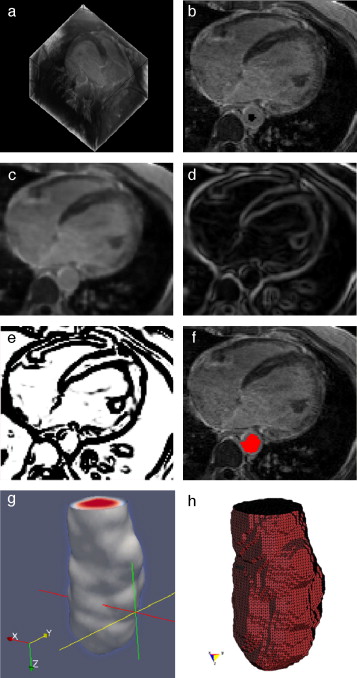

En la figura 15 se presentan los resultados obtenidos por cada etapa de procesamiento en IRM cardiovascular. Las imágenes médicas utilizadas tienen formato DICOM [39] , con 59 cortes de tamaño 192 × 192 pixels, voxel spacing: 1,5625 × 1,5625 × 2,5 mm . Por efectos de visualización, solamente se presenta uno de los cortes axiales de la imagen 3D.

Preproceso y segmentación el volumen del ventrículo izquierdo. (a) Corte axial ...

Figura 15.

Preproceso y segmentación el volumen del ventrículo izquierdo. (a) Corte axial de la IRM cardiovascular original. (b) Imagen (a) filtrada con difusión anisotrópica. (c) Imagen gradiente obtenida a partir de (b). (d) Imagen Watershed con segmentos etiquetados obtenida a partir de (c). (e) Selección del segmento del ventrículo izquierdo empleando umbralización.

En la figura 16 se presenta el volumen final del ventrículo izquierdo con el inicio de la válvula aórtica (fig. 16 .a), el modelo final suavizado visualizado en ParaView (fig. 16 .b), el modelo en sólido visualizado en Autodesk Inventor (fig. 16 .c), el modelo en malla visualizado en GiD (fig. 16 .d) y el modelo discreto con los elementos finitos realizado con Abaqus (fig. 16 .e). Estos modelos han sido obtenidos a partir de IRM cardiovascular de un paciente con cardiopatía isquémica. Obsérvese que la protuberancia presente en la zona superior derecha del ventrículo izquierdo constituye una zona de necrosis conocida como cicatriz isquémica, la cual es alojada en el músculo del miocardio.

Vista tridimensional de ventrículo izquierdo. (a) Volumen original visualizado ...

Figura 16.

Vista tridimensional de ventrículo izquierdo. (a) Volumen original visualizado con ParaView. (b) Volumen original suavizado con morfología matemática visualizado con ParaView. (c) Sólido del volumen generado con Autodesk Inventor. (d) Mallado del volumen generado con GiD. (e) Modelo discreto con el método de elementos finitos generado con Abaqus empleando condiciones de contorno de prueba.